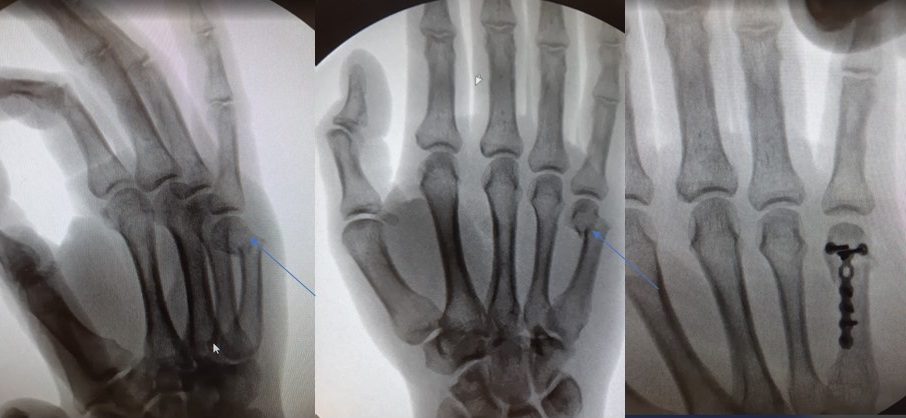

Восстановление пястных костей

Восстановление пястных костей 140 фотографий